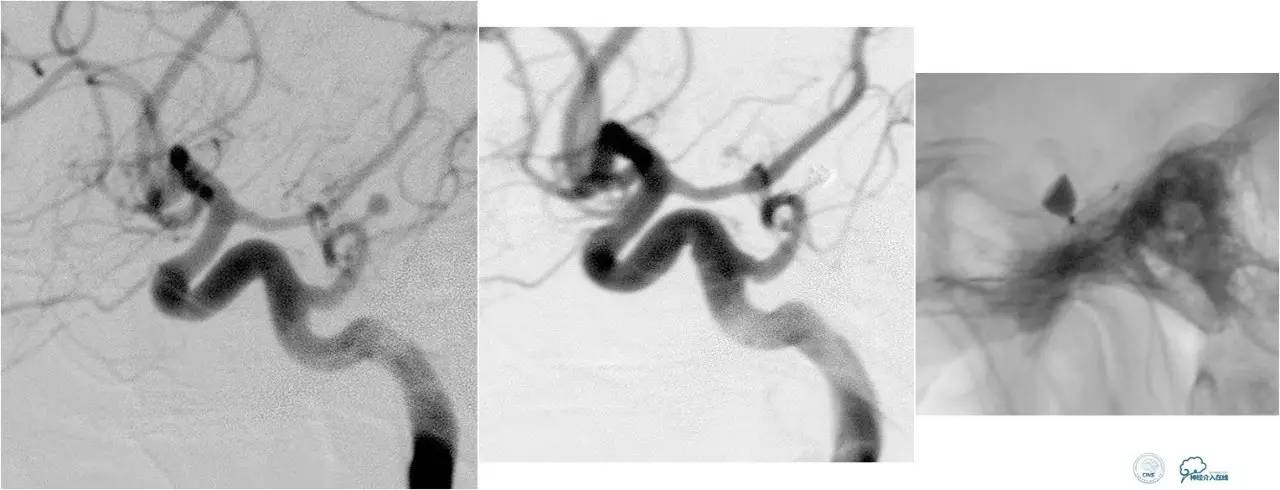

乙状窦区的DAVF,供血动脉细小,静脉引流道通畅。

同侧颈内静脉试图进入引流静脉,但是由于角度问题非常困难。

从对侧颈内静脉绕路进入引流静脉。

Sceptor球囊导管到达静脉内,充盈球囊,让后注入Onyx。

术后造影提示DAVF治愈。

海绵窦区DAVF,颈内外均参与供血。

采用净买入路,经岩下窦栓塞。

首先放入少量弹簧圈,给Onyx提供框架。

开始注入Onyx时,在颈内动脉内放入保护球囊,防止意外进入颈内动脉内。

栓塞后胶的透视影像。

最终结果,DAVF完全消失。